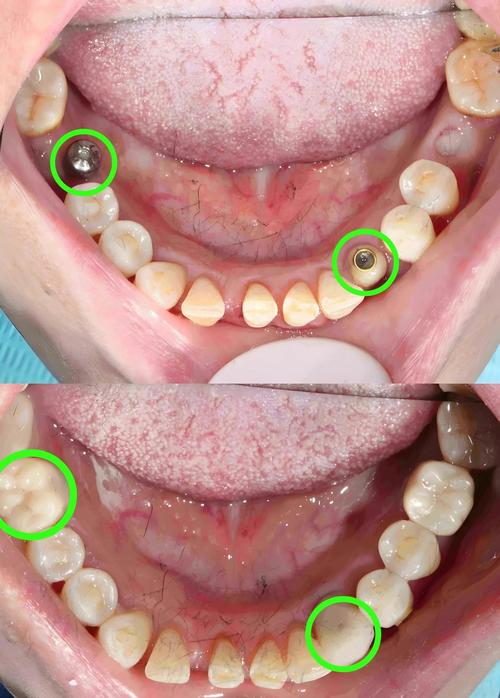

(图片来源网络,侵删)- 邻牙牙根吸收: 偏腭侧的种植体可能压迫或摩擦到邻牙的牙根,导致牙根吸收,严重时可能造成邻牙松动或丧失。